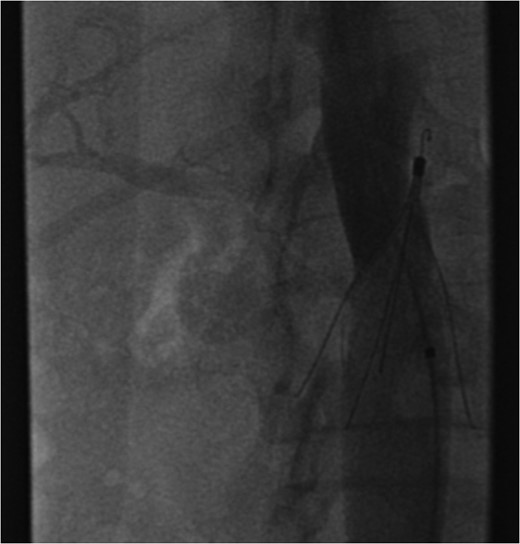

A venous phase abdominal CT demonstrating the end of the IVC filter strut penetrating the wall of the third part of the duodenum.

The patient's coagulopathy was treated and she underwent a laparotomy and evacuation of a large duodenal haematoma. After division of adhesions, a tense duodenal wall was revealed with splitting of the serosal layer. A large haematoma, of about 500 mls volume, was removed from the subserosal layer without breach of the muscularis. The penetrating strut of the IVC filter was able to be palpated within the duodenal wall but was not on view after haematoma removal. There was considerable inflammation of the retroperitoneum as well as scarring from the previous arterial bypass surgery. There was no contamination of the peritoneum with bowel contents. It was thought preferable to remove the IVC filter via the transvenous route rather than expose the IVC and risk large blood loss and arterial graft contamination in the event of duodenotomy.

Excessive tilting of the IVC filter causes the hook of the filter to appear outside of the lumen of the IVC.